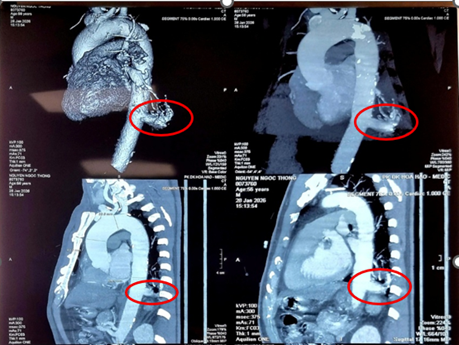

Trường hợp ông N.N.T (56 tuổi, Tây Ninh) là một tình huống hiếm gặp. Ông tình cờ phát hiện tổn thương thùy dưới phổi trái khi đi khám tổng quát. Tại Bệnh viện Bình Dân, các bác sĩ chẩn đoán ông mắc phổi biệt lập nội thùy với khối kích thước 23 mm × 26 mm. Đáng chú ý, động mạch nuôi khối này xuất phát trực tiếp từ động mạch chủ xuống với đường kính lên tới 17 mm – một kích thước rất lớn và đầy rủi ro nếu người bệnh không được điều trị.

Hình: MSCT ngực cho thấy phổi biệt lập nội thùy trong thùy dưới phổi trái, có nhánh mạch máu nuôi lớn xuất phát từ động mạch chủ ngực. (Nguồn: Bệnh viện Bình Dân)